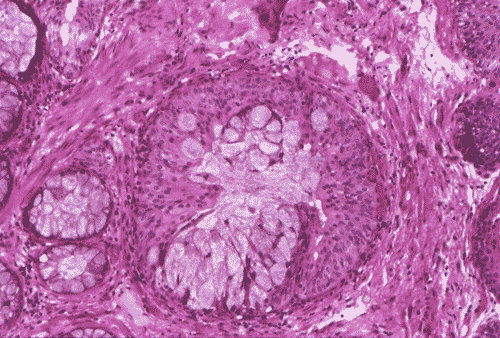

The biopsy material showed polypoid fragments with cystically dilated glands lined by columnar to cuboidal cells (Panel A, B, and C). Some of the glands were lined by transitional epithelium (Panel D), some were lined by a mixed transitional epithelium and mucin producing columnar epithelium (Panel E), and some were lined entirely by mucin producing columnar epitheliuim (Panel F) that closely resembled colonic epithelium. A mild to moderate degree of chronic inflammatory cell infiltration was also present. A mixed population of mucin producing columnar epithelium with transitional epithelium was also noted in many of the non-glandular surface epithelium (Panel G). No dysplasia was found.

DIAGNOSIS: Polypoid cystitis cystica et glandularis, intestinal type.

The typical type of cystitis glandularis contains simple cuboidal to columnar cells. Small amount of mucin may be present but the amount is usually not impressive. The intestinal type contains epithelium with intestinal metaplasia. These type has numerous goblet cells and tubular epithelium that morphologically resemble colonic epithelium and contains colonic type mucin 5, 6 . Paneth cells metaplasia can also be seen in this type. Cystitis glandularis is associated with increased risk of adenocarcinoma 1, 3, 4, 5, 7, 8. Patients with extensive and diffuse intestinal metaplasia are particularly prone to develop adenocarcinoma 8.